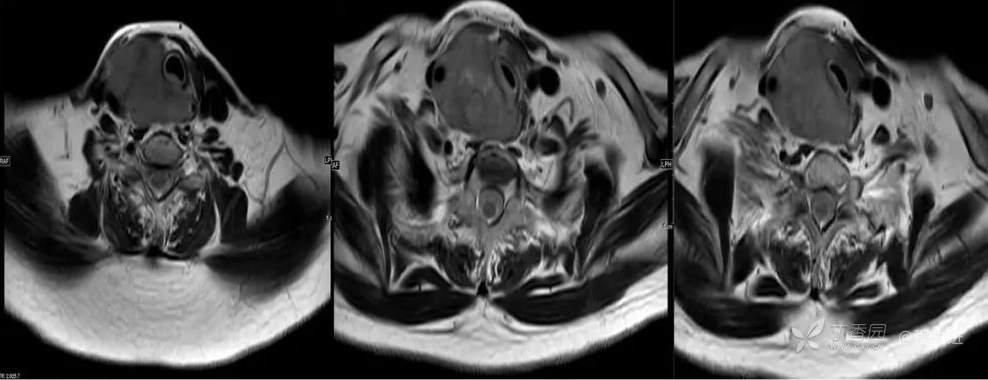

MR

T2

T2-STIR